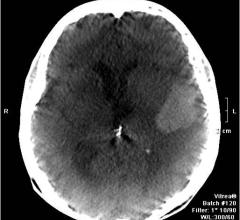

When every second counts in clinical situations such as those encountered in the emergency room and trauma centers, fast high-resolution CT scanning at low radiation dose helps radiologists render quick, confident diagnoses while keeping in mind the patient's needs. Delivering speed and performance, Philips iDose4 generates results in seconds rather than minutes, with a majority of reference protocols reconstructed in 60 seconds or less. Moreover, the Metal Artifact Reduction for large Orthopedic Implants (O-MAR) reconstruction technology reduces artifacts from metal objects, thus reducing the potential loss of critical anatomical information.Philips has taken CT scanning to a whole new level by developing medical imaging technologies that combine fast reconstruction, high image quality and low radiation dose. This advancement was brought about by Philips collaborating with Intel to enhance its imaging software to take advantage of state-of-the-art, massively-parallel computing platforms based on Intel Xeon processors.This paper details the high performance derived from Philips reconstruction technologies: Philips iDose4 and O-MAR. Some of the software optimization techniques used by Philips engineers are also described. As a next step in transforming care, Philips has launched the next innovation, called IMR. IMR is a model-based iterative reconstruction, which will run on even more powerful Intel processors and pave the way for further advances in CT imaging.